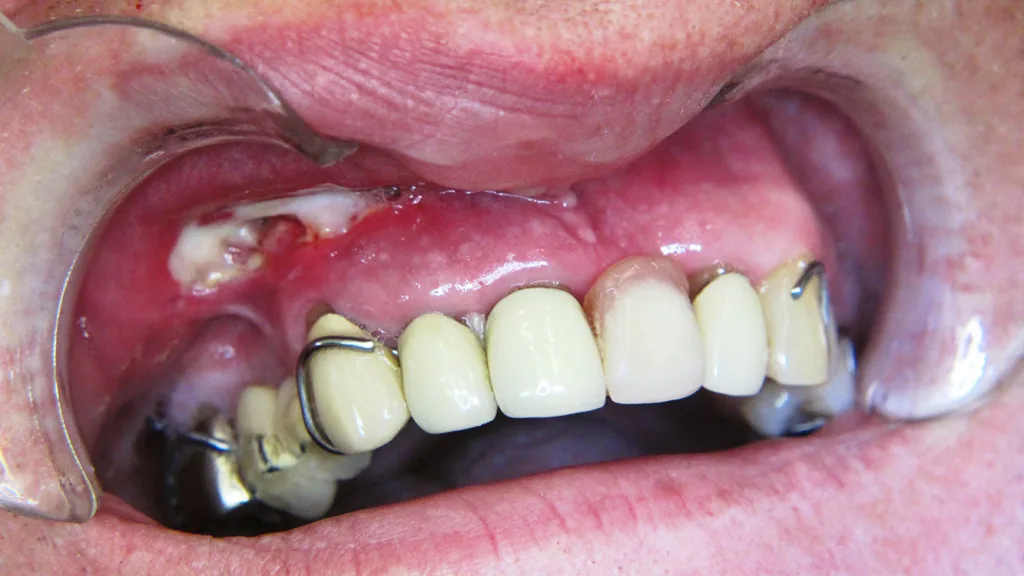

Für die meisten der genannten Substanzen liegen nur einzelne Fallberichte vor, von einer weit höheren Dunkelziffer muss ausgegangen werden. Bis auf zwei Fälle mit schwerer anaphylaktischer Reaktion handelt es sich bei den geschilderten Fällen überwiegend um leichte Reaktionen ohne irreversible Schäden [54] (Abb. 1).

Für allergische Reaktionen auf Latex (Handschuhe, Kofferdam), meist in Form von Hauthypersensitivitäten, sind in der Gummisubstanz (Naturkautschuk, Balata gutta) enthaltene Proteine verantwortlich (Abb. 1). Zur Behandlung von Personen mit bekannter Latexallergie müssen latexfreie Produkte verwendet werden [54].